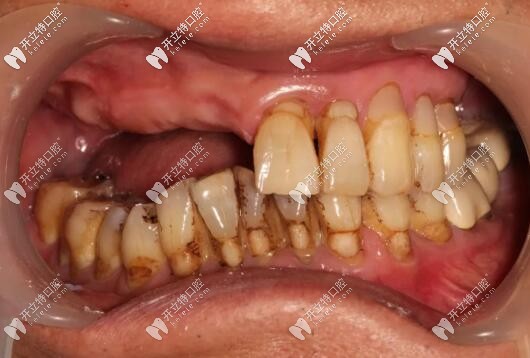

目前已完成ALL-ON-4即刻負(fù)重,通過手術(shù)情況來看,效果確實(shí)比較好,作為一位地道老陜?nèi)?,惠先生的感激之情溢于言表?/p>

西安美奧口腔即刻種植牙案例

西安美奧口腔半口種植牙案例

修復(fù)后